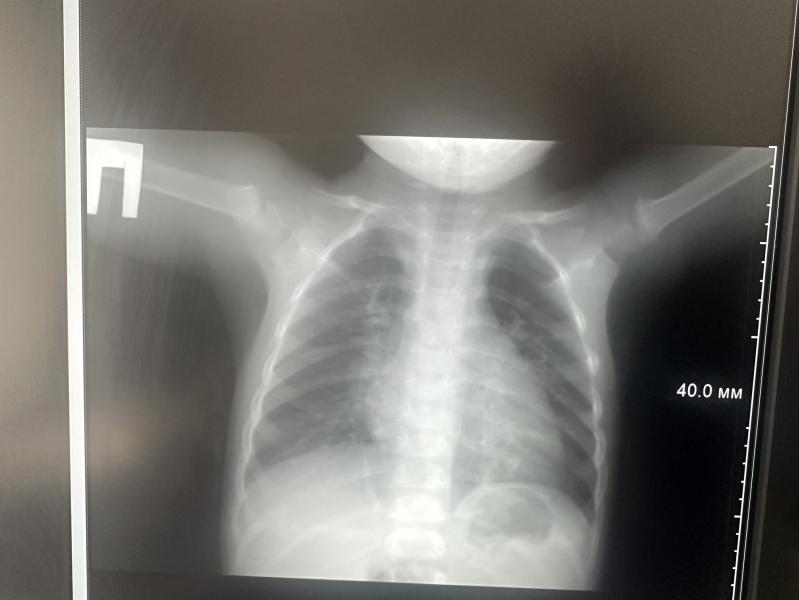

Просто капец , будьте осторожны, пневмония может быть и без температуры.

Мальчик сопливит дней 10 , промывала и все , появился кашель пару дней назад , ничего особо не давала так как считаю что сиропы бесполезны в таком возрасте , сегодня ночью был кашель каждые 10 -15 минут , спать не мог , сегодня утром мне показалось что дыхание другое , пошла не снимок и оказывается односторонняя пневмония 😟назначили лечение , в стационар не легли так как я сама могу делать уколы , год назад так же лежали в стационаре и ради одного укола в день сейчас не стала укладываться , плюс ингаляции с пульмикортом.

Вот точно такая же картина у нас , кашель буквально два дня как начался , не ожидала что будет пневмония , но по дыханию поняла что , что то не так , по этому всегда думаю лучше перебдеть и лишний раз побежать к врачу или снимок сделать

Сделали снимок там уже сказали пневмония и что нас не отпускают они.. пару дней остались , можно сказать ей 3 й день стало полностью хорошо, бегала прыгала там в больнице😹

Очаг был маленький совсем, но зато как ей стало хуже сразу с одышкой.